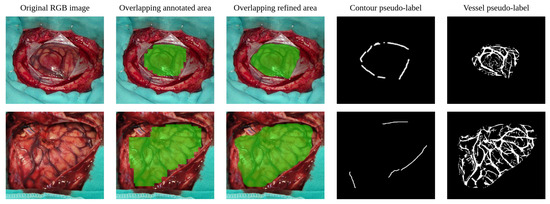

Improving Brain Tumor Detection by Cortical Surface and Vessels Segmentation Through RGB-to-HSI Transfer Learning

by Guillermo Vazquez, Alberto Martín-Pérez, Angel Perez-Nuñez, Alfonso Lagares, Eduardo Juarez and Cesar Sanz

Cancers 2026, 18(5), 857; https://doi.org/10.3390/cancers18050857 - 6 Mar 2026

Background: Accurate in vivo brain tumor detection using hyperspectral imaging (HSI), a non-invasive technique that captures spectral information beyond the visible range, is challenging due to the complexity of biological tissues and the difficulty in distinguishing malignant from healthy areas. Conventional neural-network-based methods often misclassify tumor tissue as blood vessels, largely due to high vascularization and the scarcity of annotated data. Method: To address this issue, this work proposes an underexplored approach that decomposes the problem into two tasks: (1) segmentation of the brain cortical surface and its blood vessels, and (2) segmentation of biological tissues within the segmented craniotomy site. The cortical segmentation task is addressed independently of the segmentation model used in the second stage. To achieve this, a set of pseudo-labels is generated from RGB and HSI captures acquired during in vivo brain surgeries. These pseudo-labels support a multimodal training strategy that leverages both imaging domains, yielding a model capable of segmenting the craniotomy site and the blood vessels contained in it. The model is further refined on HSI using weakly supervised fine-tuning with sparse ground truth annotations. Results: The final segmentation map combines cortical and tissue segmentation outputs, considering only cortex pixels not overlapped by vessels as potential tumor regions. This simplifies the HSI tissue segmentation task, reframing it as a binary segmentation of healthy vs. other tissues, while still enabling a comprehensive multiclass output. Conclusions: The proposed method achieves up to a 15.48% increase in F1 score for the tumor class, while segmenting the brain cortex with a mean Dice similarity coefficient (DSC) of 92.08% and accurately detecting 95.42% of labeled blood vessel samples in the HSI dataset. Full article